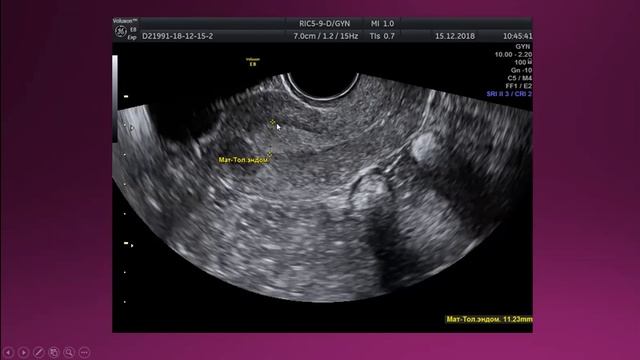

Узи и н шип

Узи и н шип 113 фотографий